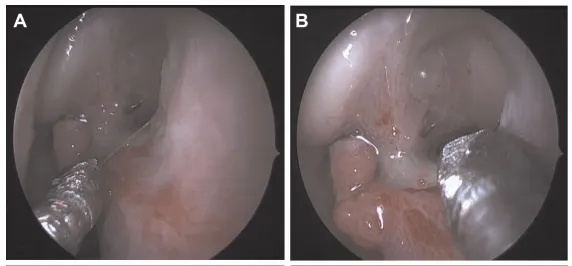

▼中鼻甲(MT)侧移后,鼻腔探查右鼻窝,证实鼻中隔有大穿孔,黏膜呈白色(图A和B)。

▼由下向上、由后向前切开右侧下鼻腔粘膜斜向切开(图C和D)。